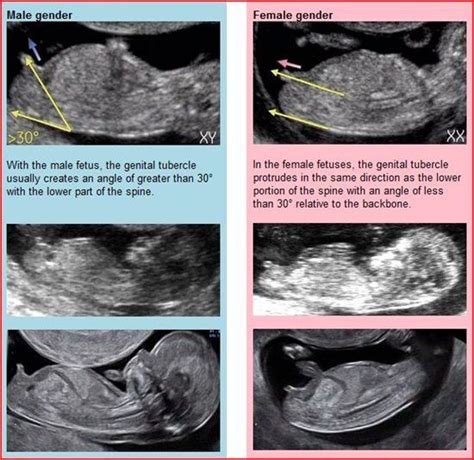

If you are really itchy to start baby shopping have an elective scan done to. This will push your uterus up and make a clear view of your baby. At 12 weeks, we may be able to use ultrasound to determine gender based on the angle of the genital tubercle.

This is sometimes called “nub theory.” This is sometimes called “nub theory.” Using this method, the sonographer looks at whether the tubercle is pointing up toward the baby’s head, which indicates a boy, or whether it remains. BUT at my 12 week the tech said she was pretty certain we were having a girl. 12 Weeks Pregnant Ultrasound Your fetus at 12 weeks is almost done developing their body’s important systems and parts, which means it’s all about getting bigger and more mature from here on out.

The nub theory 12 week ultrasound is an great tool for many soon-to-be parents to see the defined gender markers of their baby before the genitalia is fully formed. At 12 weeks pregnant, your baby weighs about 0.49 oz (14 g). When you see your baby, you’ll notice they are starting to look more like a baby and less like a tadpole.

According to proponents of nub theory, you can crack the code of your baby’s sex at a 12-week ultrasound.It’s true that between 8 and 9 weeks of gestation the genital tubercle begins to take. It truly is astonishing how fast they grow inside your womb. 12 week ultrasound / boy or girl CVD1985.